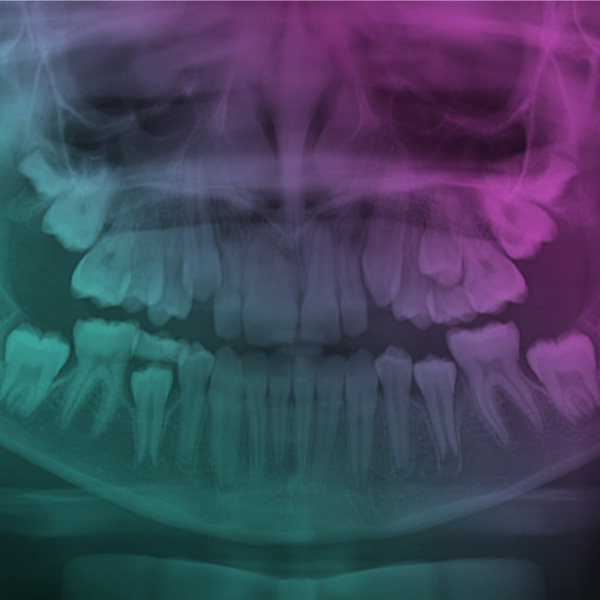

Os exames radiográficos são utilizados em praticamente todas as especialidades da Odontologia, como ferramentas complementares no processo de diagnóstico. Nesta palestra serão abordados tópicos atualizados a respeito das principais técnicas radiográficas e suas indicações, com enfoque na Atenção Primária em Saúde.